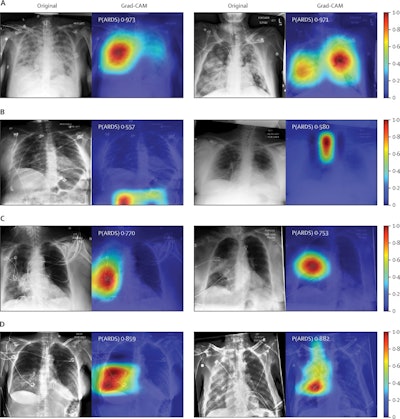

Chest radiographs were grouped based on CNN probabilities of ARDS and physician ARDS annotations; gradient-weighted class activation mapping (Grad-CAM) was then used to localize areas used by the CNN to identify ARDS within the radiographs. The heat map illustrates the importance of local areas within the image for classification. The importance value is scaled between 0 and 1 where a higher number indicates that the area is of higher importance for classifying the image as consistent with ARDS. (A) Chest radiographs annotated as ARDS by six of six physicians and assigned a high CNN probability. (B) Chest radiographs scored as consistent by six of six physicians but assigned a lower probability by the CNN. (C) Chest radiographs annotated as ARDS by zero of six physicians but assigned a high probability by the CNN. (D) Chest radiographs with disagreement among physicians (three of six physicians annotating ARDS) and assigned a high probability by the CNN. P(ARDS): probability that the chest radiograph is consistent with ARDS. Image courtesy of Lancet Digital Health.Visual evaluation of the algorithm outputs confirmed that it learned to focus on regions of the lung that exhibited opacities when classifying images as consistent with ARDS. Performance of the algorithm was consistent with or higher than individual physician performance, the researchers wrote.